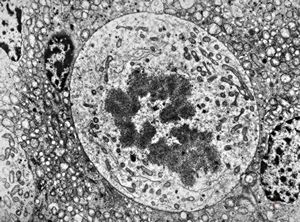

M,39y. | mitosis - chromophobic pituitary adenoma